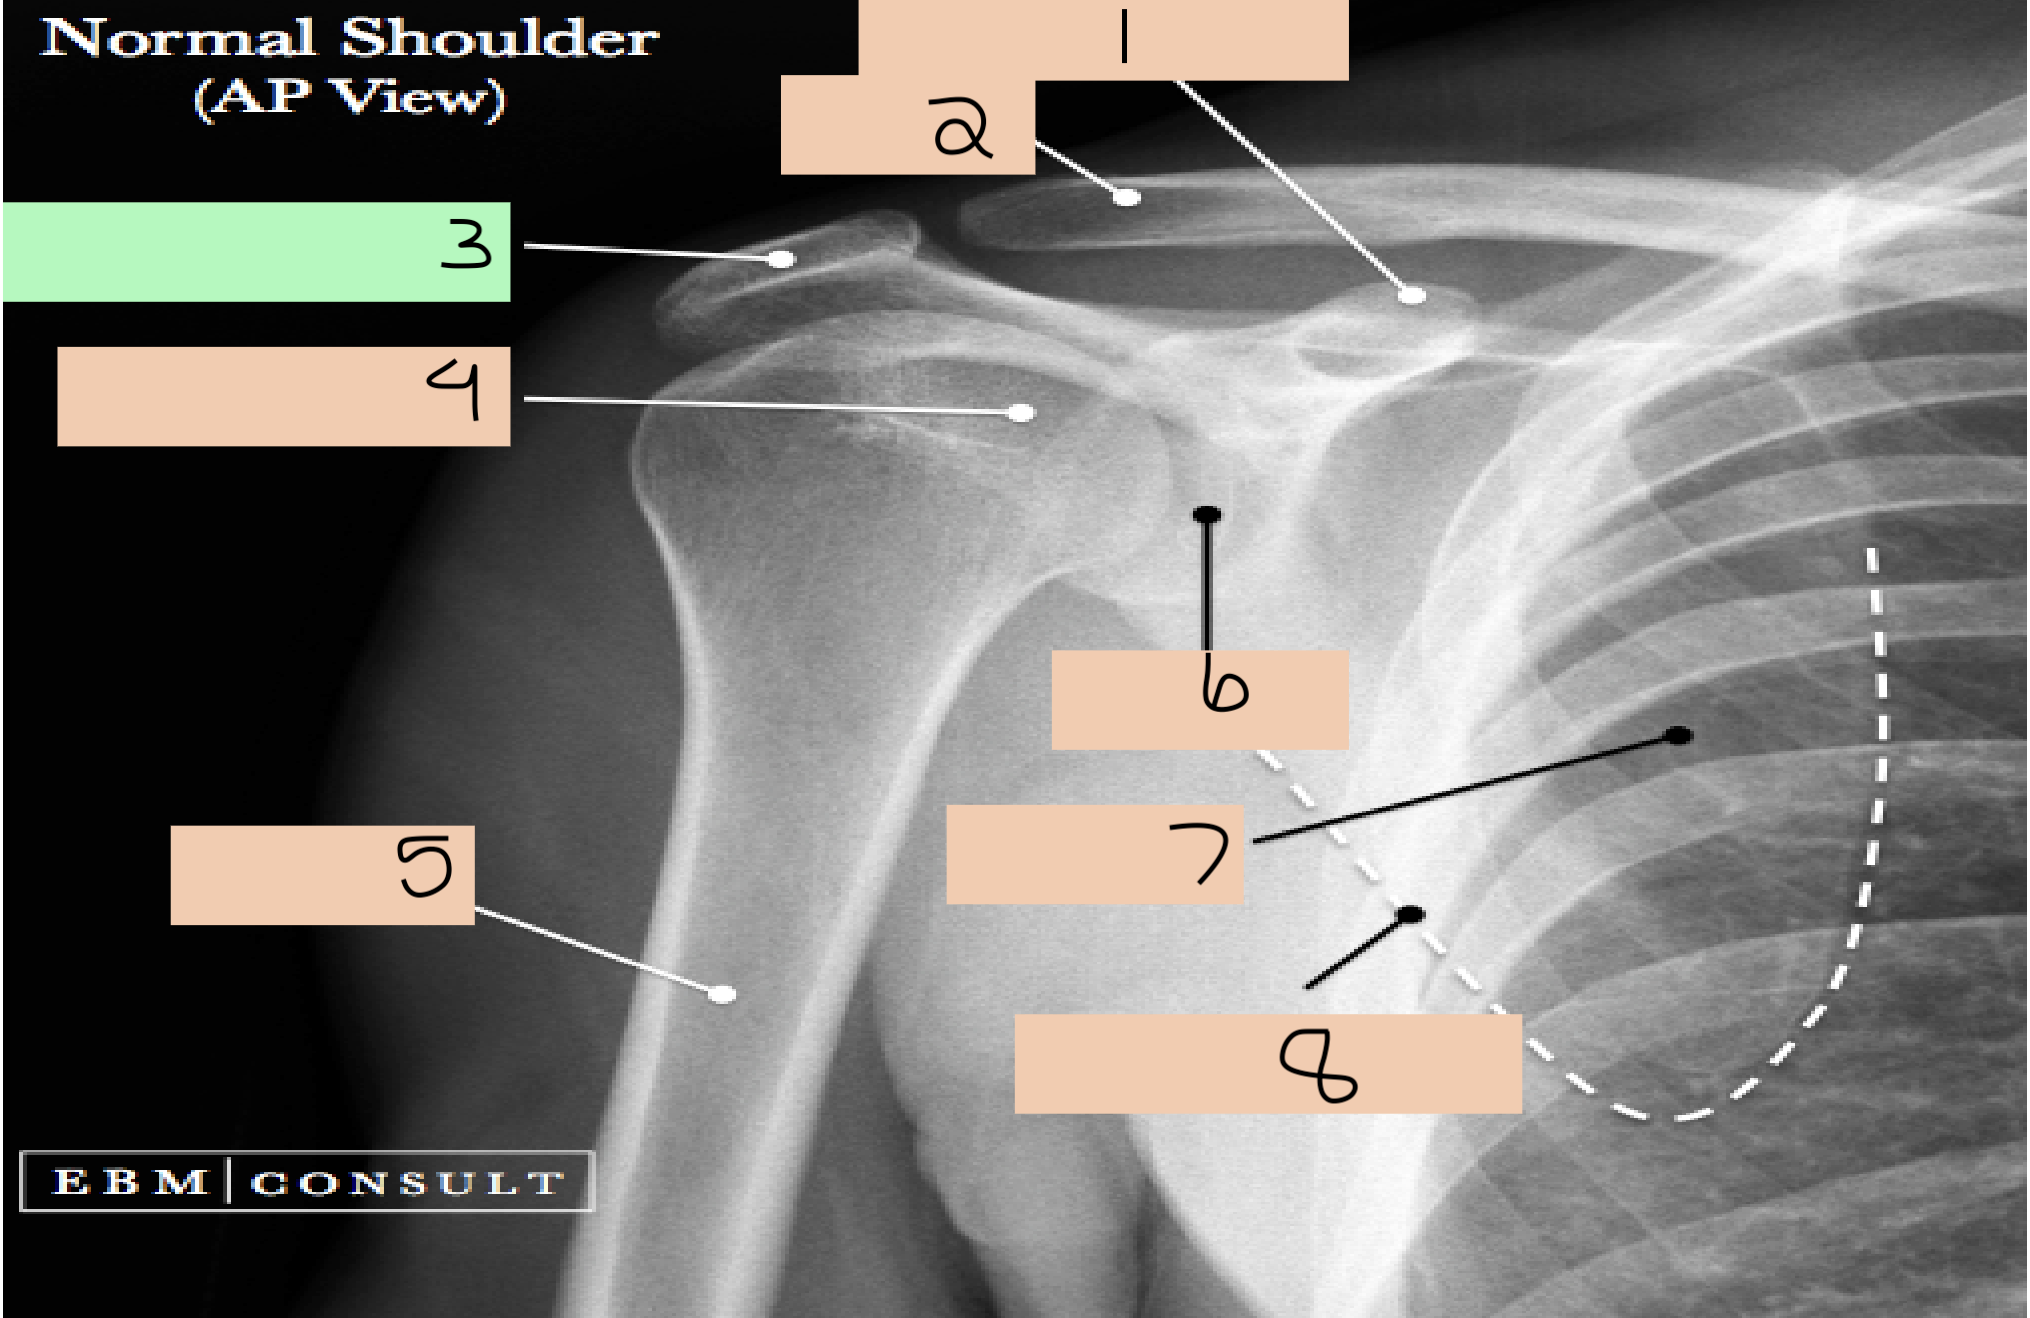

1

coracoid process

2

clavicle

3

acromian

4

head of humerus

5

lateral border scapula

6

shaft of humerus

7

inferior angle scapula